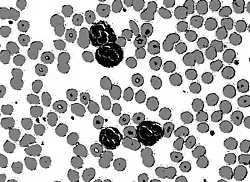

Circular thresholding is an algorithm for automatic image threshold selection in image processing. Most threshold selection algorithms assume that the values (e.g. intensities) lie on a linear scale. However, some quantities such as hue and orientation are a circular quantity, and therefore require circular thresholding algorithms. The example shows that the standard linear version of Otsu's method when applied to the hue channel of an image of blood cells fails to correctly segment the large white blood cells (leukocytes). In contrast the white blood cells are correctly segmented by the circular version of Otsu's method.